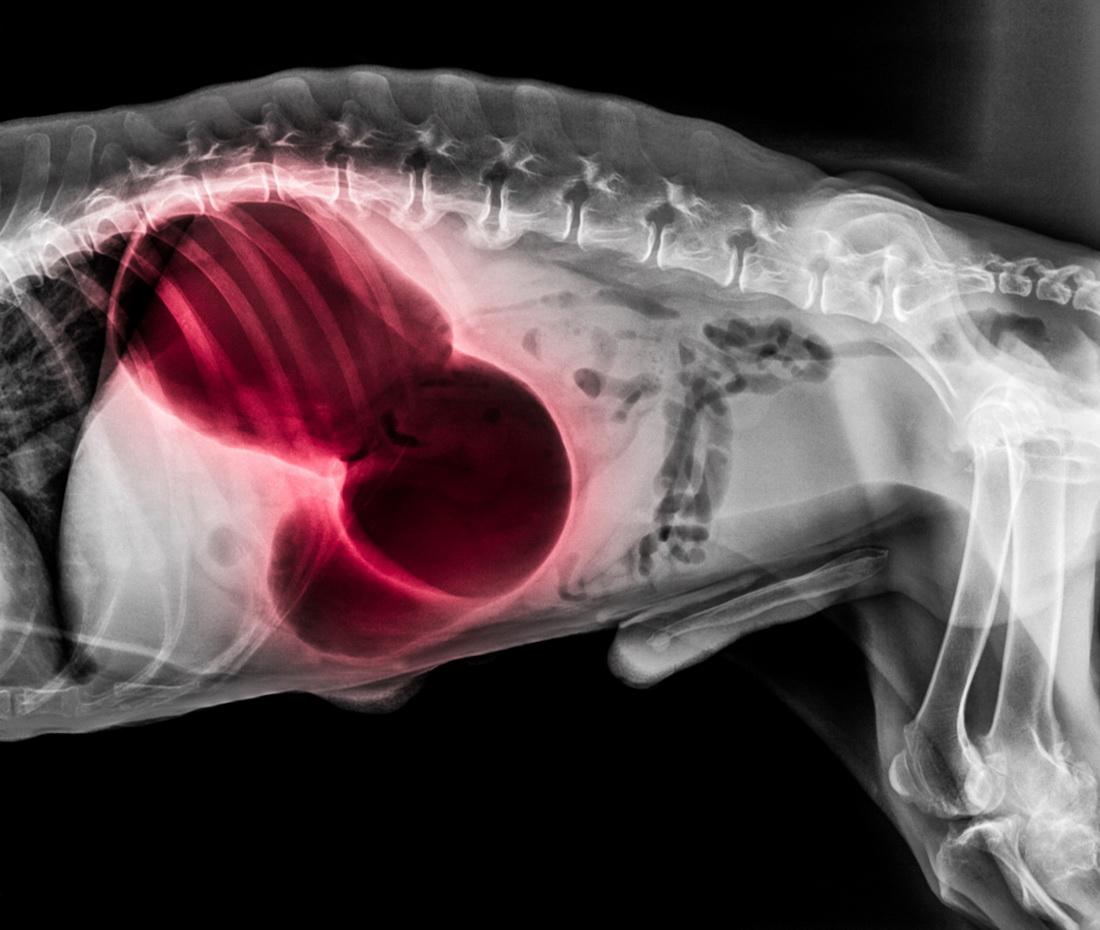

Pokud máte podezření na torzi žaludku, je opravdu nezbytné co nejdříve dorazit k veterinárnímu lékaři. Čím dříve se psovi dostane veterinární péče, tím se zvyšuje jeho šance na přežití. Pro potvrzení či vyloučení torze se provádí rentgenové vyšetření, následuje operace. Operační zákrok spočívá v přístupu do dutiny břišní, odsátí vzduchu ze žaludku, návratu žaludku do přirozené polohy a kontrole sleziny. Po těchto úkonech většinou následuje zavedení sondy přes dutinu ústní a jícen do žaludku a opakovaný výplach žaludečního obsahu. V případě přítomnosti větších cizích těles se musí provést otevření žaludku a jejich odstranění.